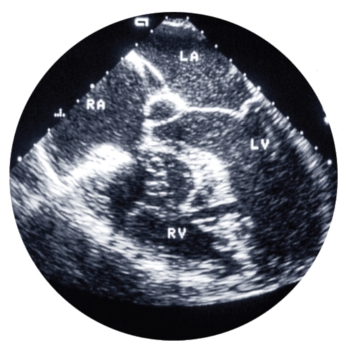

Ecocardiografia este prima investigaţie în cazul suspectării existenţei unei afecţiuni valvulare; aduce informaţii importante atât despre cauza disfuncţiei valvulare cât şi despre severitatea acesteia.

Examinarea ecografică în urgenţă prezintă numeroase avantaje: poate fi efectuată la patul bolnavului, fiind disponibilă pe scară largă, poate fi efectuată în ortostatism (ortopnee), este neinvazivă. Poate fi efectuată şi de medicii anestezişti intraoperator. Dacă ecografia transtoracică (TTE) nu confirmă o suspiciune clinică înaltă de afectare valvulară severă, în special disfuncţie de proteză, atunci este necesară cea transesofagiană (TEE).

Ecografia cardiacă reprezintă investigaţia de elecţie în toate aceste patologii. Cu acurateţe mai mare, însă cu disponibilitate mult mai mică, se poate efectua ecografie transtoracică 3D, iar standardul de aur devine ecografia transesofagiană 3D.